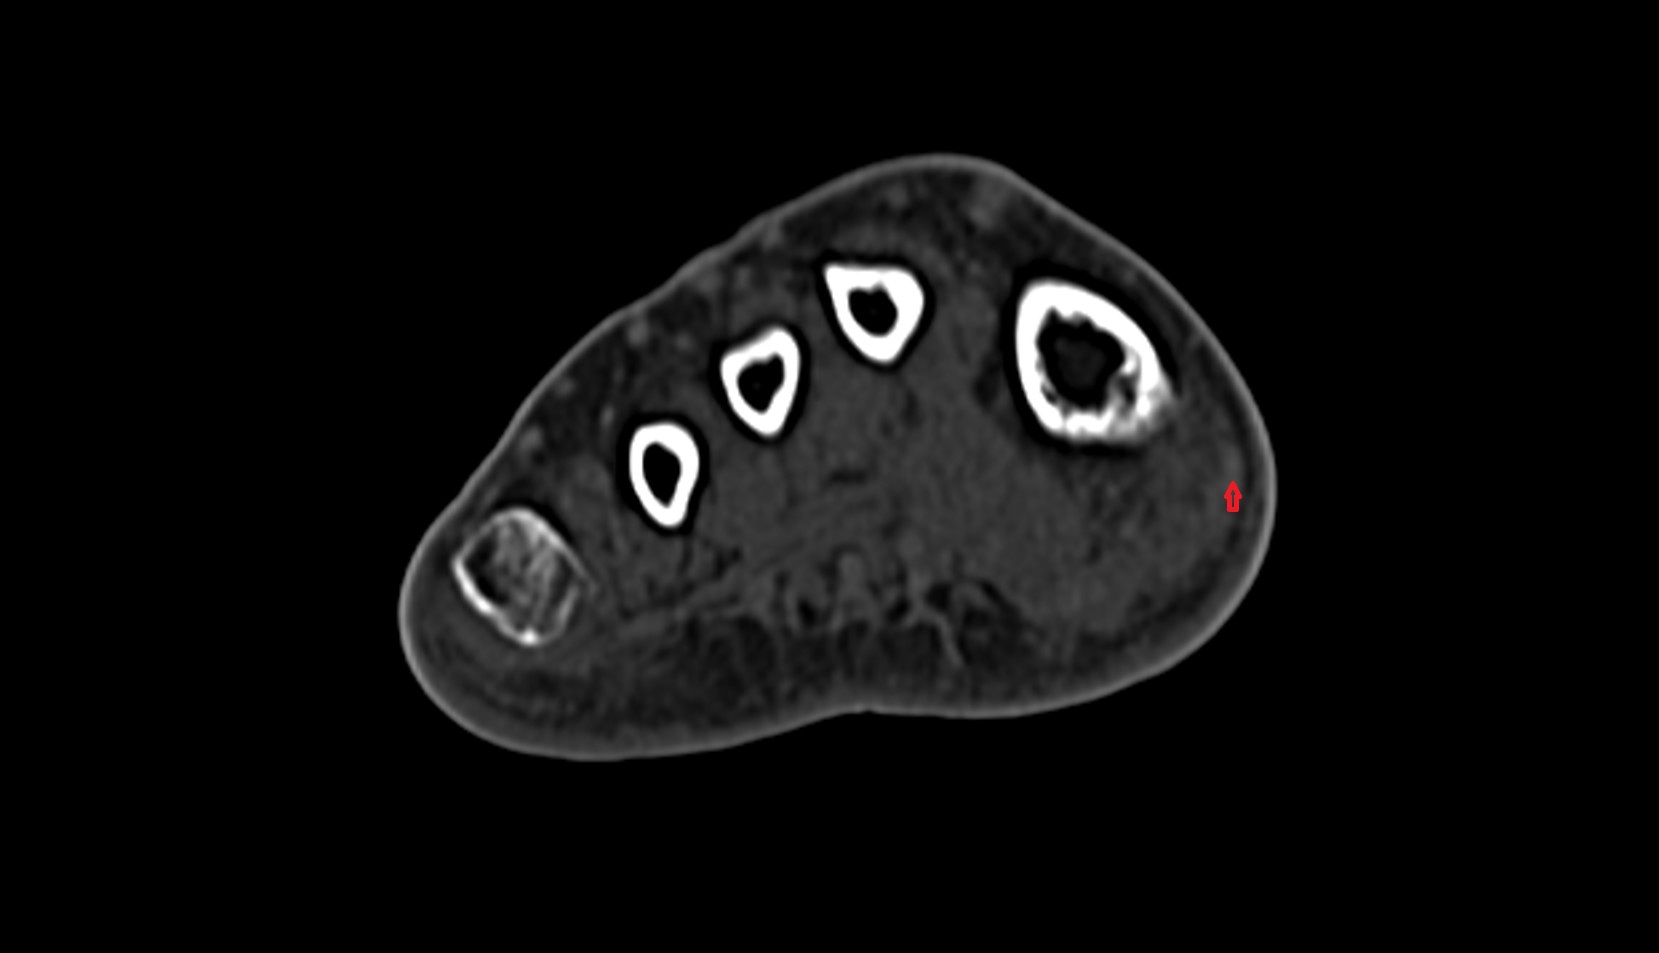

- Talus

- Calcaneus

- Medial malleolus

- Lateral malleolus

- Ankle joint

- Fibula shaft